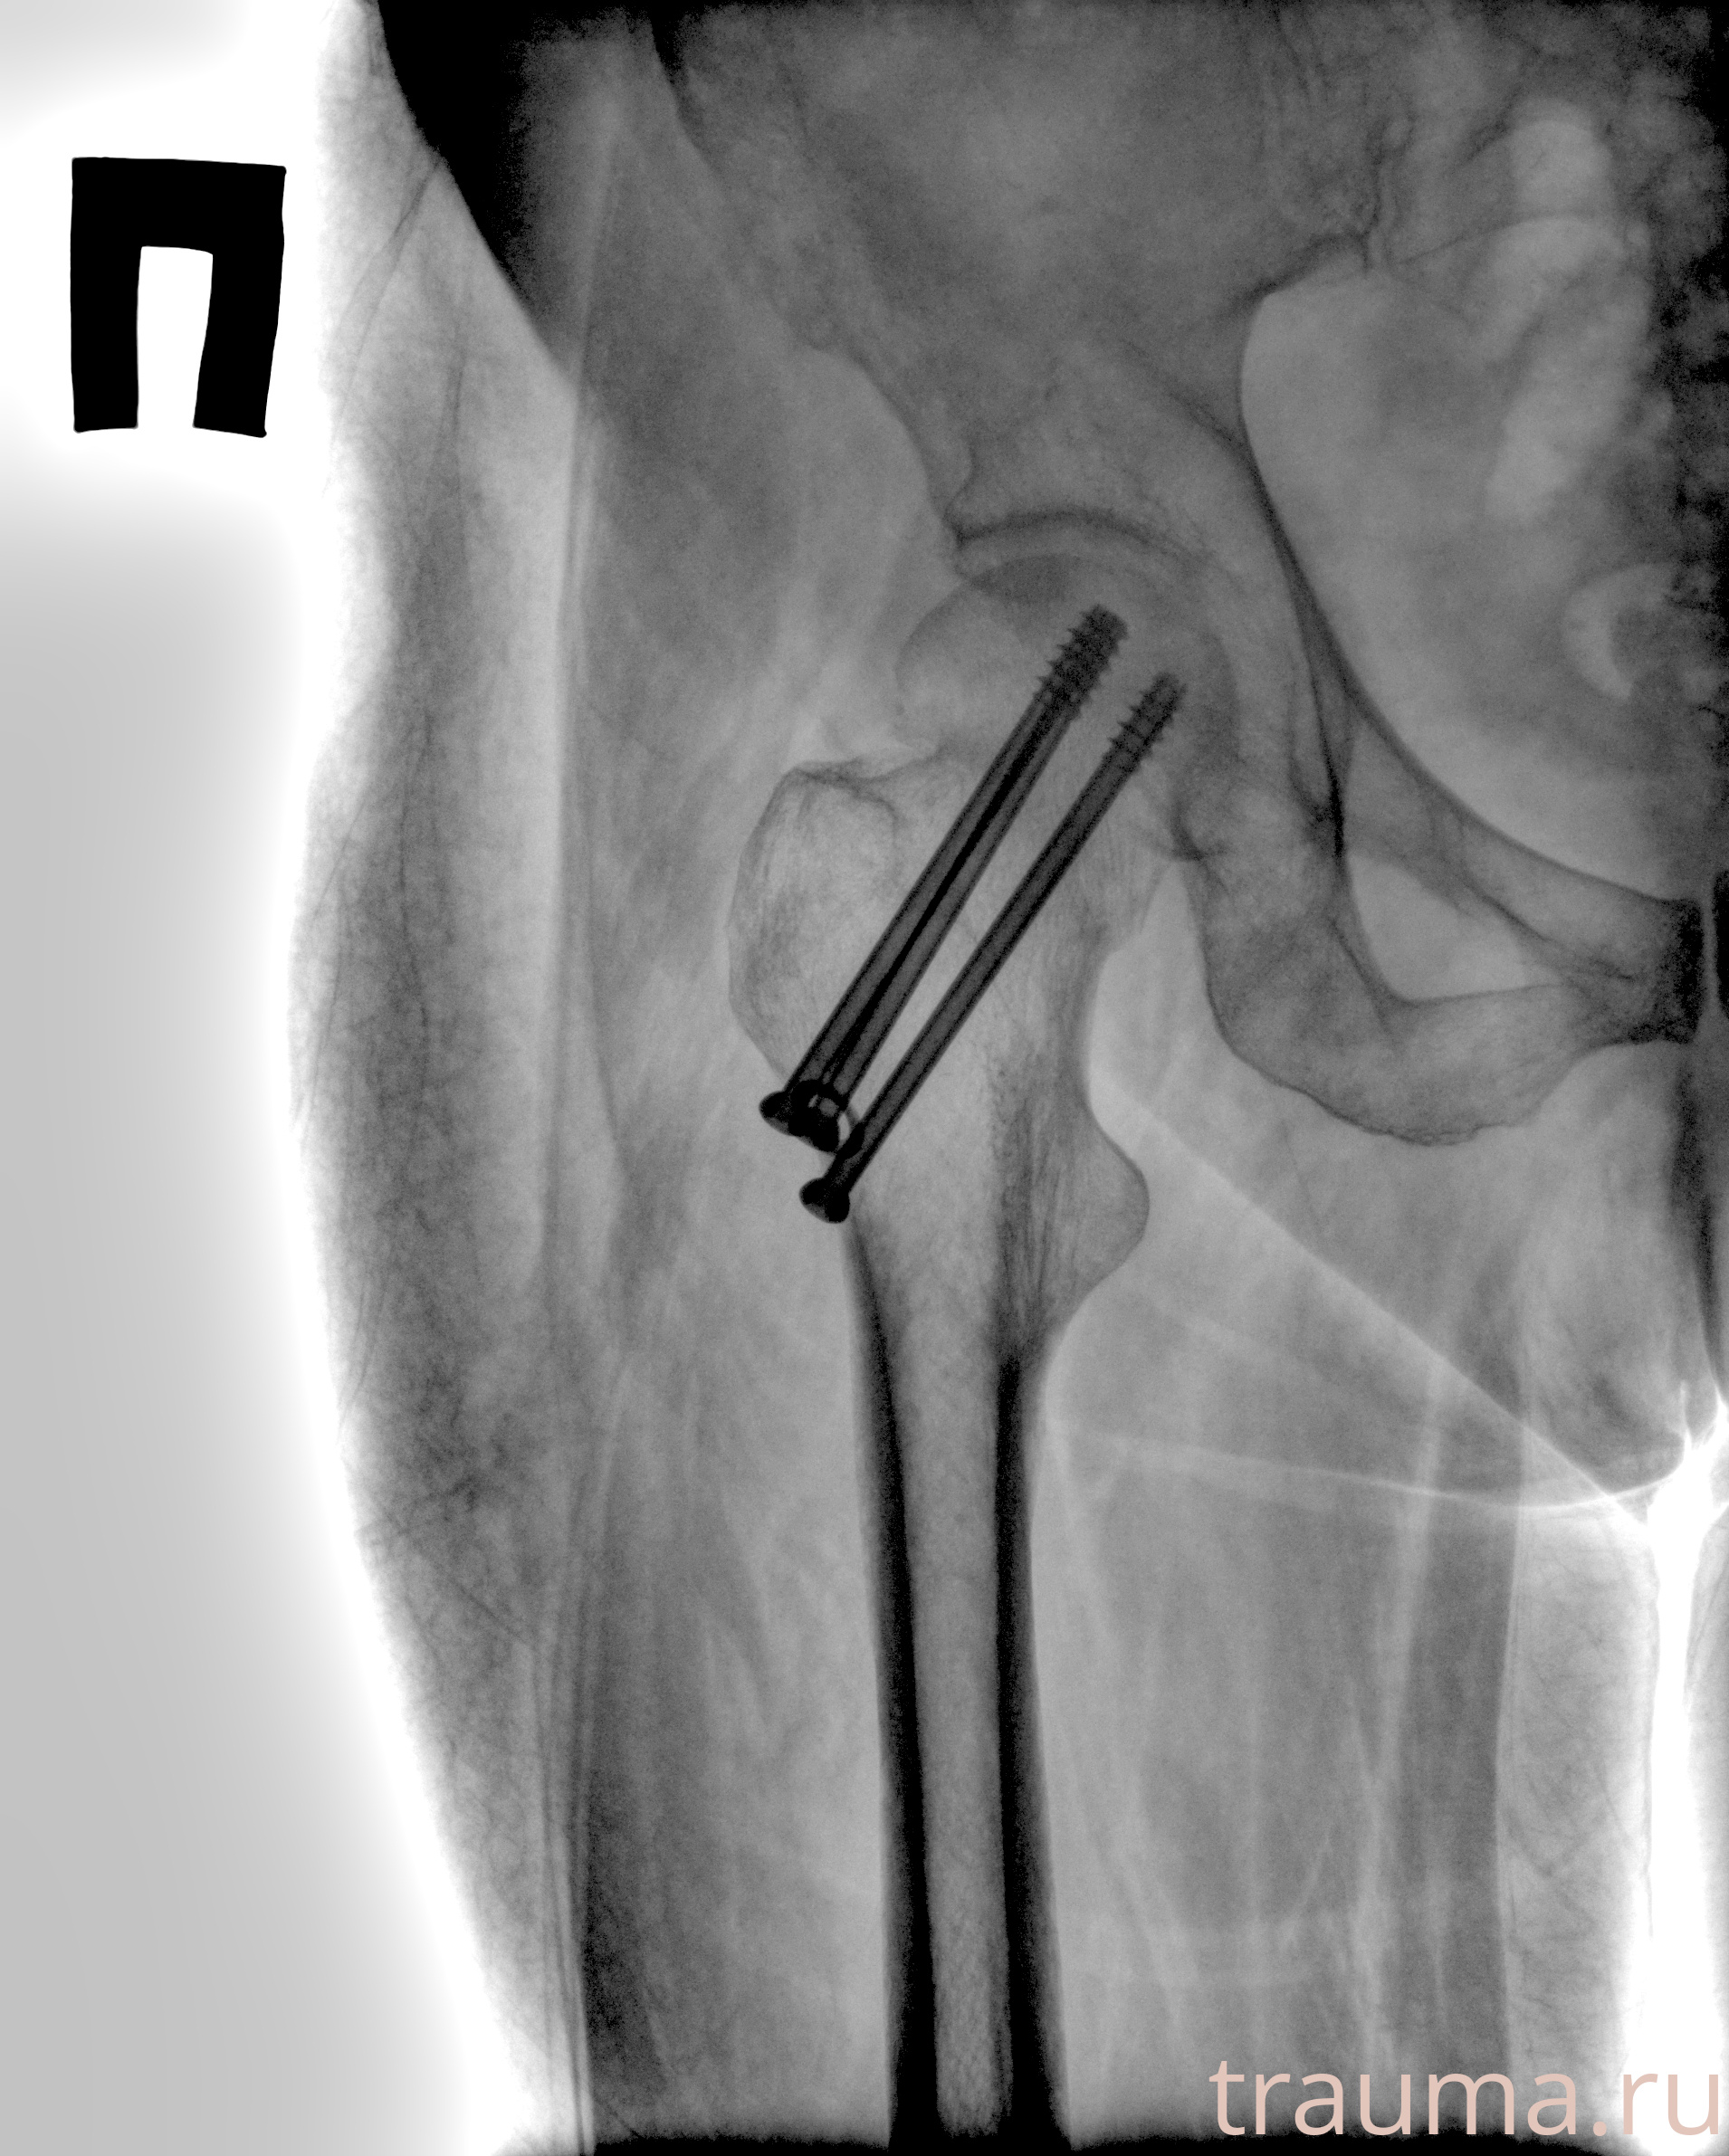

Рентгенограммы

Рентген на дому: по вашему адресу приезжает врач-рентгенолог, травматолог-ортопед с мобильным рентгеновским аппаратом, проводит диагностику травмы или заболевания, делает необходимые рентгенограммы, дает рекомендации по дальнейшему лечению. Получить качественные снимки в домашних условиях возможно благодаря уникальной методике, разработанной МосРентген Центром для института  Склифосовского